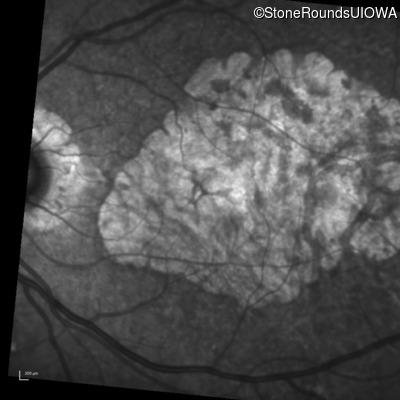

Infrared Fundus Photograph - Right - 20/25

Exemplar

Infrared Fundus Photograph - Left - 20/32 -2